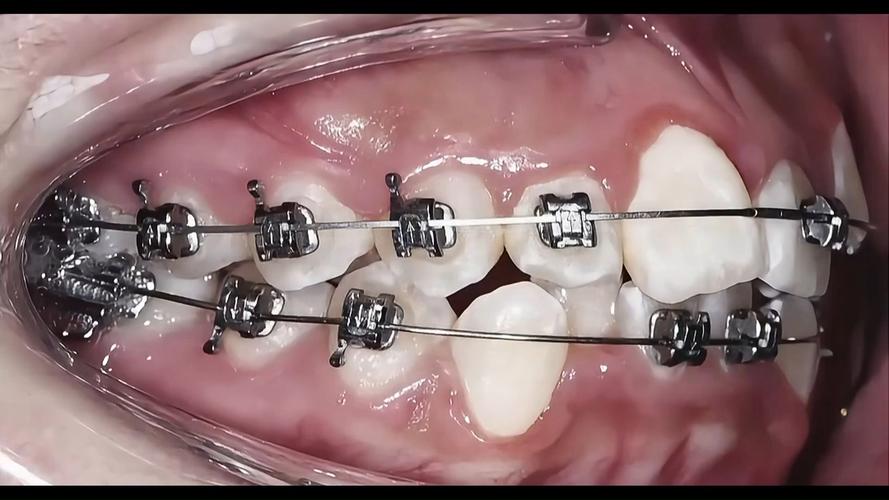

- 截骨:根据术前设计的截骨线,使用超声骨刀或摆动锯精确截骨(如上颌Le Fort I型截骨、下颌矢状劈开截骨)。

- 骨块移动与固定:将截开的骨块移动至理想位置,通过钛板钛钉进行内固定,确保骨块稳定。

- 牙齿调整:对个别牙齿进行去骨、修整,确保咬合紧密。